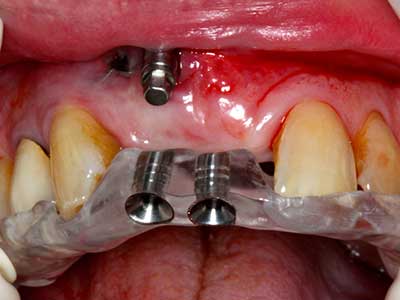

Fig. 14: Incorporación de cuatro implantes RSX cónicos (Bego Implant Systems, Bremen).

Fig. 15: El control radiológico realizado al cabo de un año muestra una estabilidad del nivel óseo.

Fig. 16: También condiciones intraorales estables con incorporación de los implantes en la encía queratinizada.